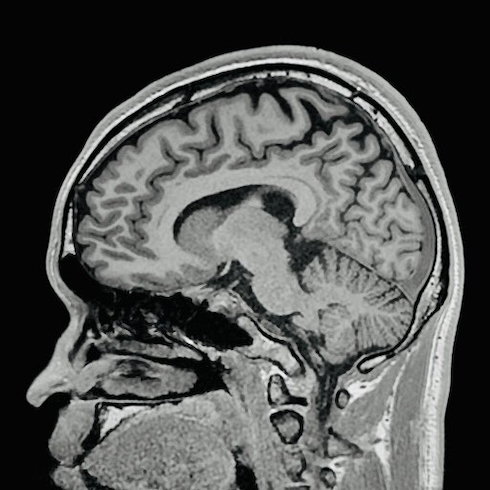

今回は、研究のために撮影した自身の脳のMRI画像が注目を集めました。投稿した2枚の写真では、横からの断面はごくごく普通の頭部に見えますが、上からの断面は邪悪な笑みを浮かべる口のように見える部分が存在しています。

真田さんは「『俺の頭ってこうなってるのか〜』って感心してたら、急に闇堕ちした熊のプーさん登場してやばかった」とコメントしました。確かに、口の少し上がクマの鼻、その両側が不気味な笑みを浮かべる目、上端の眼球部分がクマの耳と考えると、2023年公開のホラー映画「プー あくまのくまさん」に登場する“闇堕ちしたプーさん”にそっくりです。